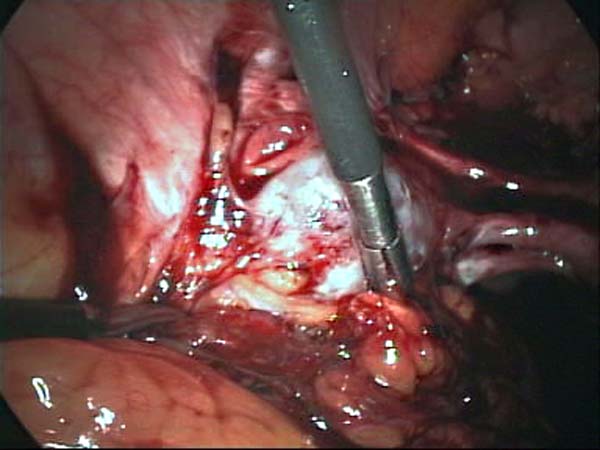

- Laparoscopy Photos 1

- Laparoscopy Photos 2

- Laparoscopy Photos 3

- Laparoscopy Photos 4

Laparoscopy Photos Polycystic Ovaries adhesiolysis IUCD Through Uterine Wall | Dr N Layyous